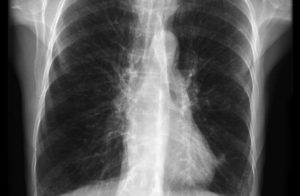

Врач должен провести обследование и выслушать жалобы больного, чтобы диагностировать воспаление бронхов и определить его форму. Для определения пораженных участков можно использовать УЗИ и рентгеноскопию, а анализ мокроты в лаборатории поможет выявить возбудителя заболевания и назначить соответствующее лечение.

Флюорография может выявить очаг воспаления в бронхах и помочь выяснить истинную причину возникновения заболевания.